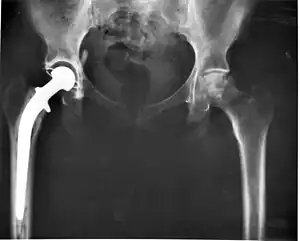

Remplacement total de l'articulation de la hanche. La hanche droite de ce patient (à gauche sur la photo) a été supprimée par une articulation artificielle. L'articulation artificielle mime les formes naturelles, la tête du fémur étant intégrée par une tête métallique insérée dans la moële de l'os, et s'insérant dans une cupule en plastique blanc insérée dans le bassin. L'une des raisons les plus fréquentes de remplacement de l'articulation de la hanche est souvent l'arthrose.